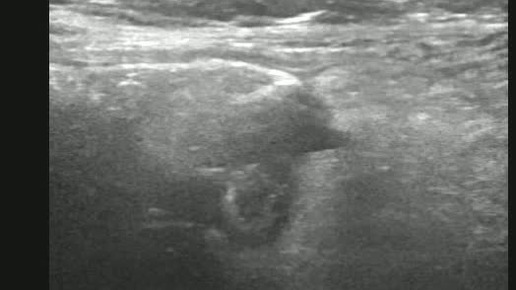

Ультразвуковые находки от врача УЗД Зорина Я.П.